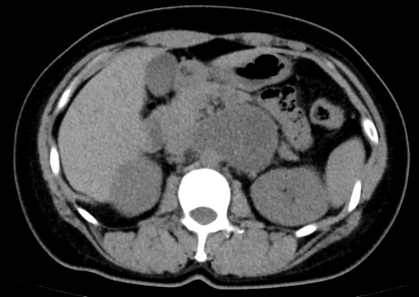

l CT:腹膜后偏左囊实性团块,边界清,增强实性部分不均匀轻中度强化,5.3*7.8*5.9cm,临近组织受推压。